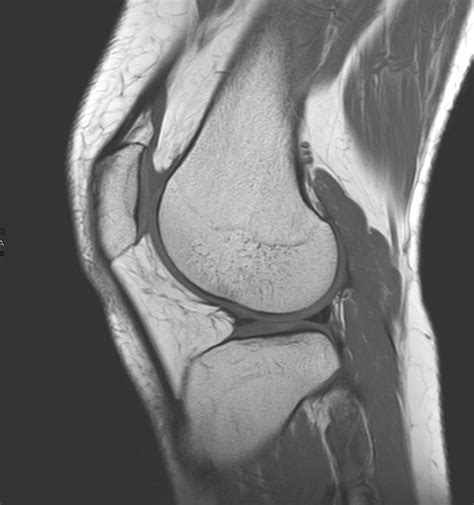

A bucket handle injury is a specific type of meniscal tear where the torn piece of the meniscus flips into the joint space, resembling the handle of a bucket. This type of tear is often more severe and can cause the knee to lock or give way. The meniscus is a C-shaped piece of cartilage that cushions the knee joint and helps distribute weight evenly. When it tears, it can lead to a range of symptoms that affect mobility and quality of life.

• Imaging Tests: X-rays, MRI, or CT scans may be ordered to visualize the meniscus and confirm the diagnosis. MRI is particularly useful for detecting meniscal tears and assessing the extent of the damage.